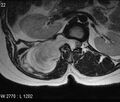

Chondrosarcomas represent approximately 25% of primary bone tumors. Unlike osteosarcomas, they are more common in elderly patients, mostly in men (female: male ratio is 1: 2, in spinal lesions this ratio is up to 1: 4). In most cases, these are malignant primary tumors, but there are also secondary chondrosarcomas that have grown on the basis of initially benign neoplasia, such as osteochondroma.. [22][23]

Within the spine, they most often occur in its thoracic part, although spinal chondrosarcomas represent only 7% of all these tumors. As in the case of osteosarcoma, they most often occur in the long bones. The therapy is primarily surgical, but chemotherapy or radiotherapy may be applied depending on the type and behavior of the tumor. [24][25][26]náhled|MRI – metastáza prsního karcinomu

Secondary extradural tumors[edit | edit source]

Secondary tumors of the spinal cord are caused by metastases of cancers from various areas of the body. The most common cancers are lung, breast, prostate, kidney, thyroid [2][3]. Extradural metastases represent about all 95% of spinal metastases [27].